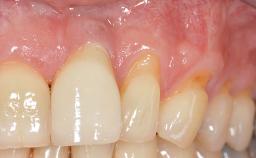

Periodontal Plastic Surgery and Prosthetic Procedures to Treat Peri-Implant Soft-Tissue Dehiscences

A 30-year-old woman was referred by her general dentist for evaluation of an esthetic complication related to previous implant treatment for congenitally missing maxillary lateral incisors. The patient’s chief complaint was the inadequate esthetic appearance of her smile. The case demonstrates the use of a combined approach to achieve optimal results. Two different flap designs - a tunnel technique and a coronally advanced flap - are employed based on the surgical objectives for the affected site.

Soft Tissue Grafting Yes